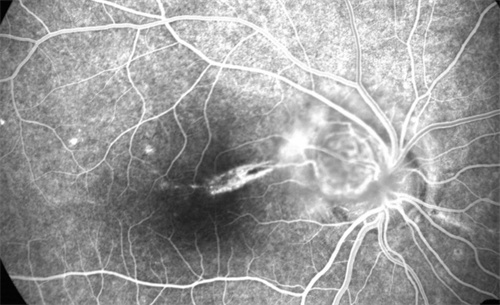

例如,高度近视患者因眼轴较长,常伴随视网膜变薄,动态光学区可减少对眼底的压力,降低术后并发症风险。

适用人群:高度近视、远视及合并视网膜病变患者,如糖尿病视网膜病变术后矫正。

价格区间:单眼价格约12000-15000元,定位中高端市场。